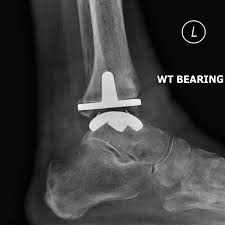

Total ankle replacement removes and then replaces both sides of the ankle joint with specially designed components, called prostheses. The tibial prosthesis consists of a polyethylene (medical grade plastic) and titanium base plate tray that is inserted into the tibia and fibula, giving the implant a wide base for support.